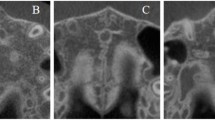

CBCT voxel-based maxillary superimposition

T1 and T2 CBCT scans were superimposed using Dolphin 11.8 Premium (Dolphin Imaging & Management Solutions, Chatsworth, CA, USA)19. The head position was calibrated to set the axial sections parallel to the Frankfort horizontal plane to make sure the selected superimposition region basically consistent among all the patients. Three landmarks were chosen in the Side-by-Side Superimposition tab to primarily align the two images. Voxel-based superimposition was performed on the Overlay Superimposition tab; the maxillary structures were selected by the red subregion box (Fig. 2). Oriented post-treatment CBCT was exported as Digital Imaging and Communications in Medicine (DICOM) format. The surface model mesh clearly showing the dental crown areas of the hard structures of T1 and T2 CBCT scans were exported into STL format.